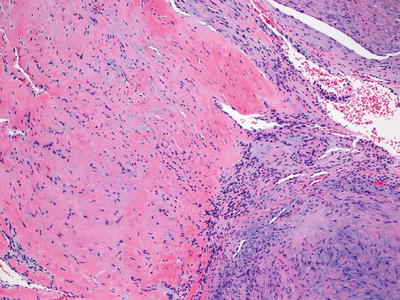

Fig. 24.11

A spindle cell proliferation is present within a background that is focally myxoid and fibrotic in myoepithelioma